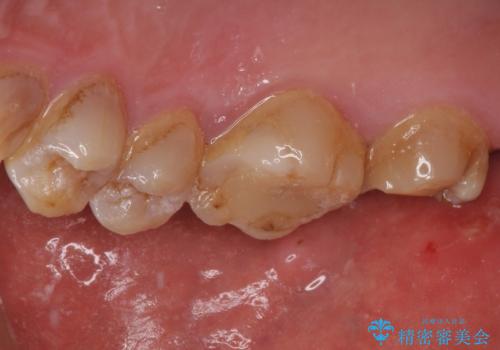

- 銀歯が外れてしまったとのことで来院された患者様です。

上顎奥の粘膜に近い部分で、外れた銀歯の下には大きく虫歯が広がっていました。

虫歯をしっかりと取り除き、ゴールドインレーにて修復することとしました。